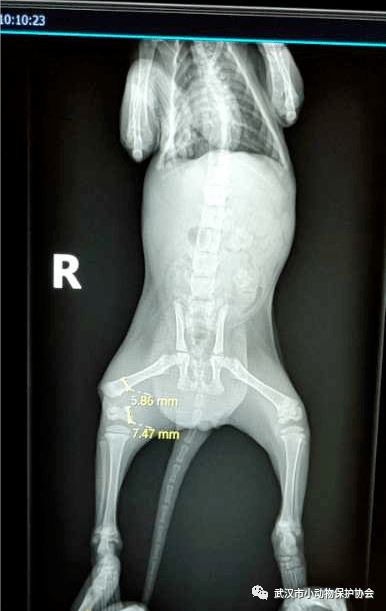

卓刀泉一小区的业主联系协会,她救助了一只后腿受伤的小猫,自己送往医院检查,医生预估手术费用较高,她无力承担,然后联系到了协会,经过沟通商议,她表示可以出猫咪一部分的费用。

小橘猫的骨折比较严重,手术矫正恢复良好,两周后顺利出院。小橘猫接受领养。小橘猫的手术和住院费用是1800元,救助人承担了800,还有 1000元空缺。